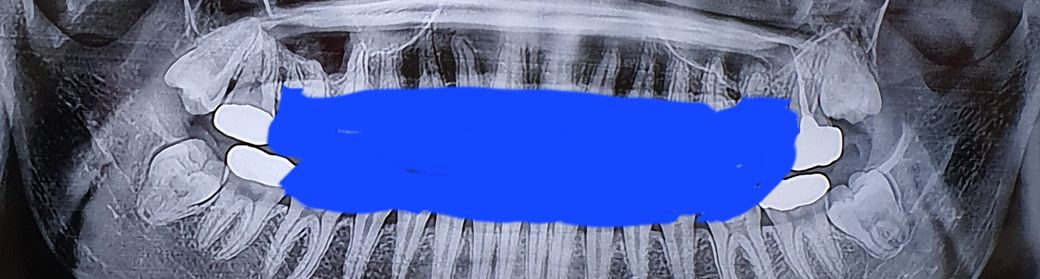

일반치과의원에서 할 수 있는 난이도이나 아래 사랑니의 경우 신경관과의 위치를 ct사진 찍어서 확인하고 조심해서 접근할 필요는 있어보입니다

아래 사랑니의 경우 두번째 큰 어금니를 밀고있는 양상입니다. 멀쩡한 두번째 큰 어금니의 뿌리 흡수, 치근 우식을 야기할 가능성이 있습니다.

매복 사랑니의 경우 예방적 발치가 권장되는 것은 아니지만 위와 같은 경우 위에서 언급한 문제를 일으킬 가능성이 있어 보이긴 합니다.